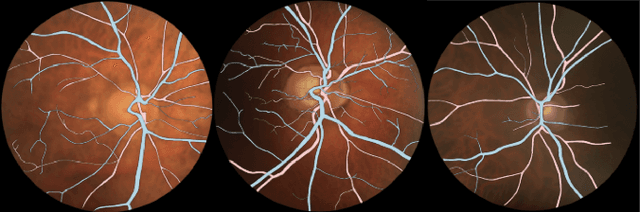

Abstract:The retina is the only part of the human body in which blood vessels can be accessed non-invasively using imaging techniques such as digital fundus images (DFI). The spatial distribution of the retinal microvasculature may change with cardiovascular diseases and thus the eyes may be regarded as a window to our hearts. Computerized segmentation of the retinal arterioles and venules (A/V) is essential for automated microvasculature analysis. Using active learning, we created a new DFI dataset containing 240 crowd-sourced manual A/V segmentations performed by fifteen medical students and reviewed by an ophthalmologist, and developed LUNet, a novel deep learning architecture for high resolution A/V segmentation. LUNet architecture includes a double dilated convolutional block that aims to enhance the receptive field of the model and reduce its parameter count. Furthermore, LUNet has a long tail that operates at high resolution to refine the segmentation. The custom loss function emphasizes the continuity of the blood vessels. LUNet is shown to significantly outperform two state-of-the-art segmentation algorithms on the local test set as well as on four external test sets simulating distribution shifts across ethnicity, comorbidities, and annotators. We make the newly created dataset open access (upon publication).